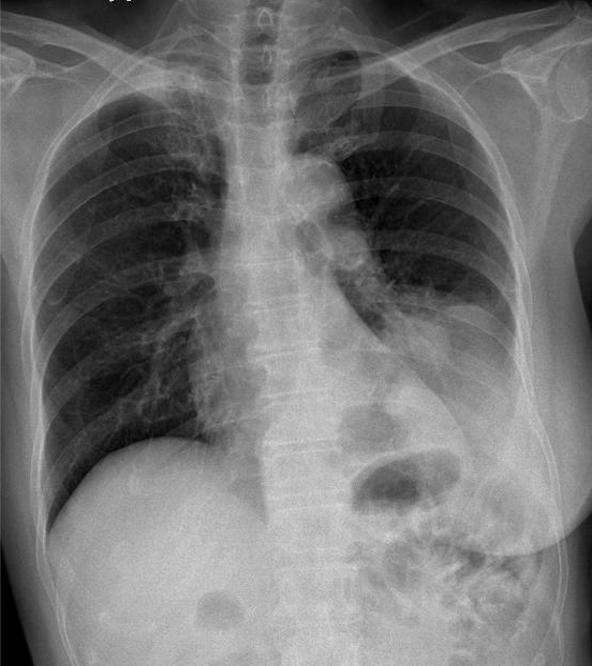

1-Xơ rải rác thùy trên phổi (P) 2-U thùy dưới phổi (T) 3-Tràn dịch màng phổi (T) 4-Cung động mạch chủ đóng vôi